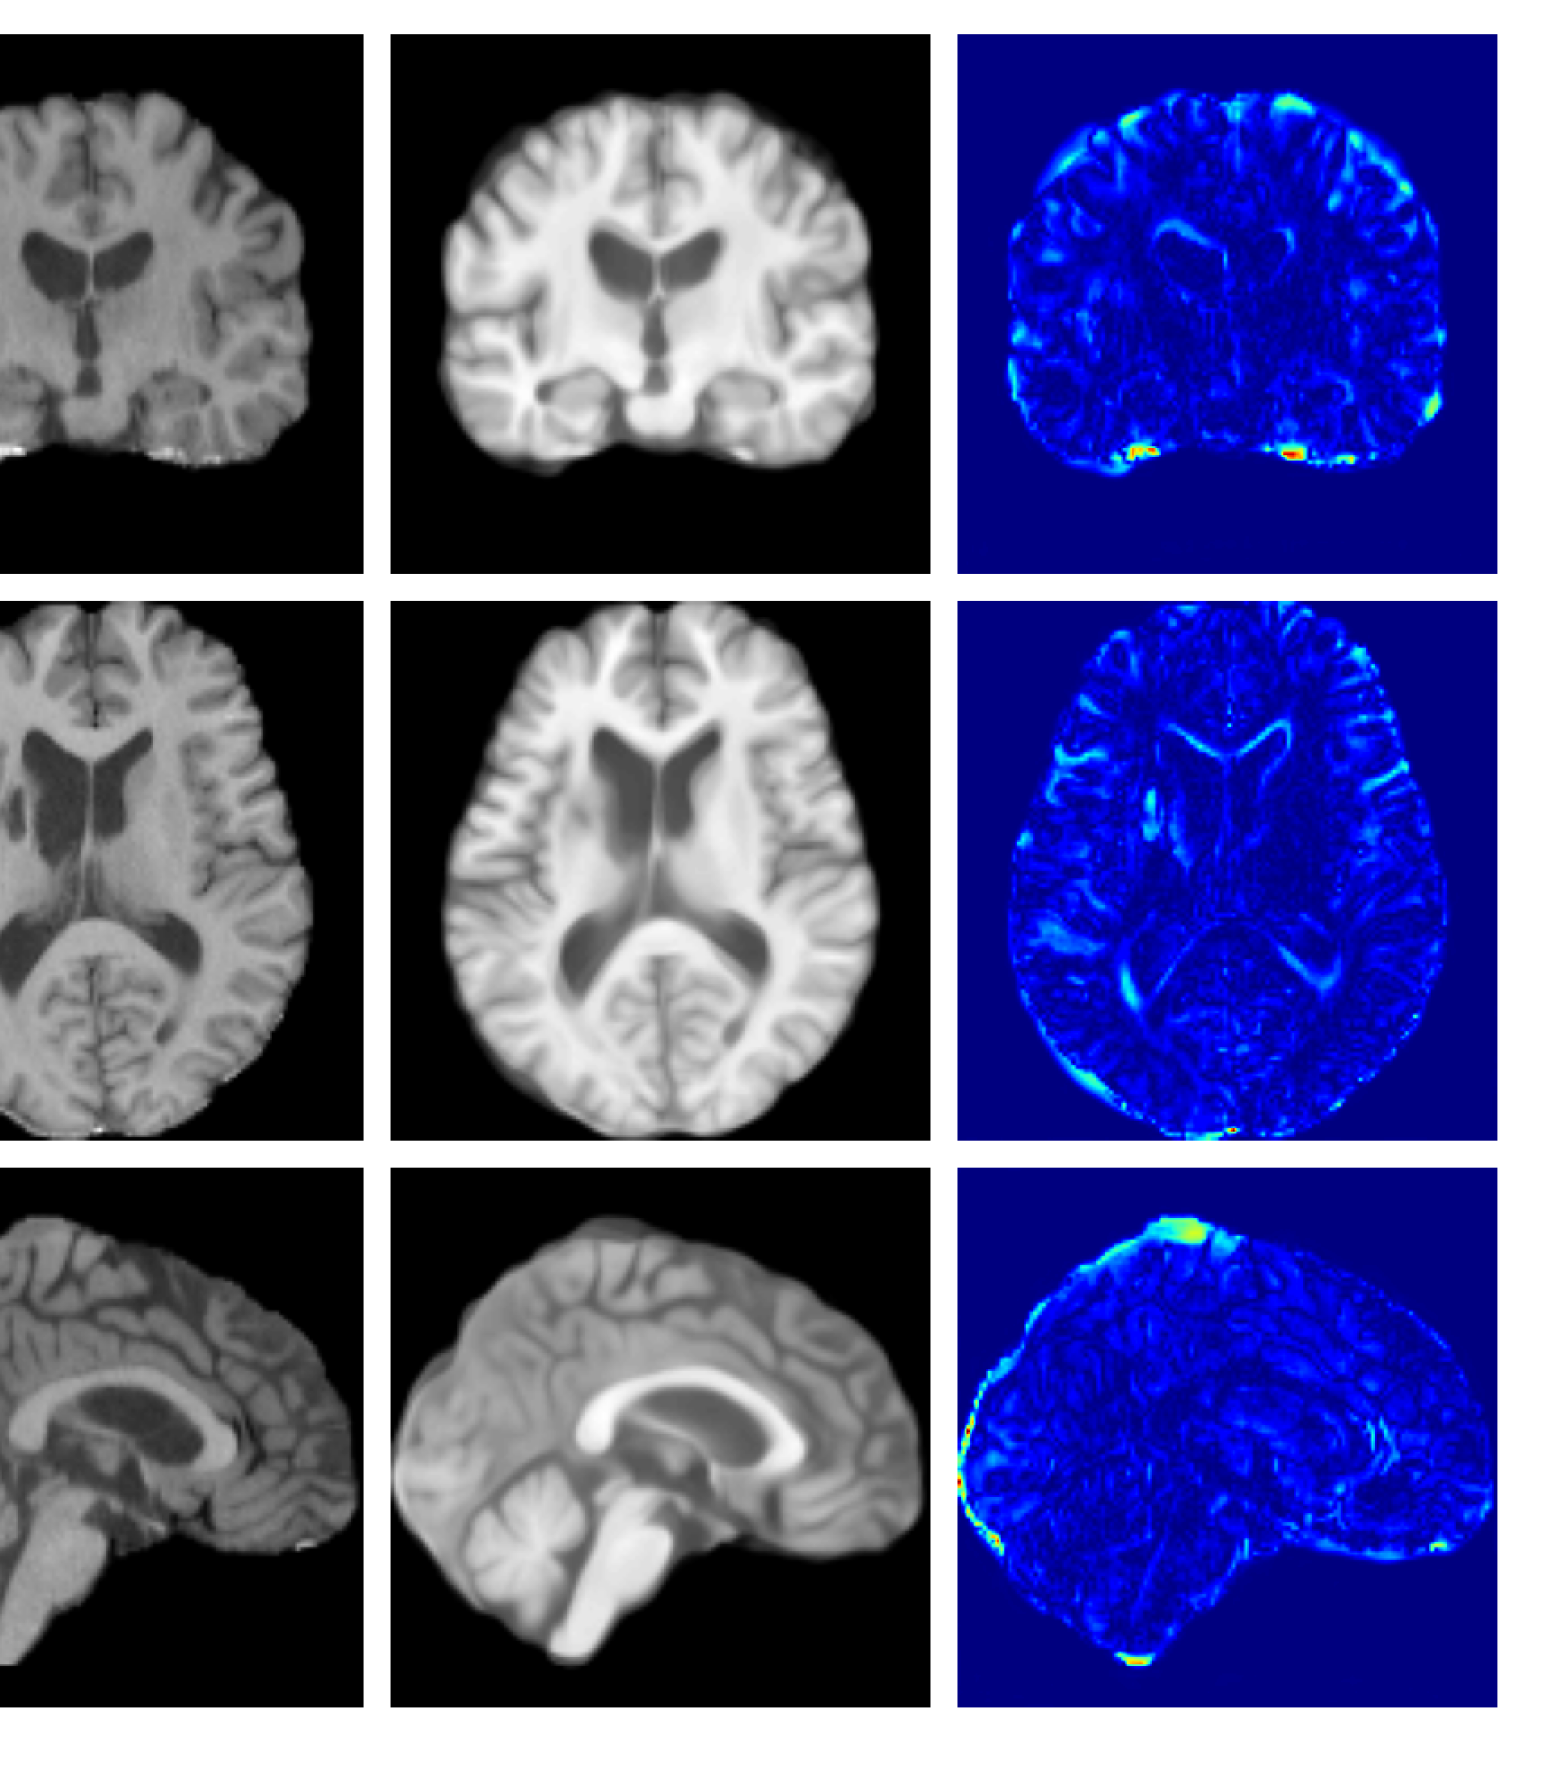

Figure 3: Example reconstructions and anomaly maps for a sample from the disease cohort of the UKBB dataset. Lesion and WMH are indicated in the original image by the red and yellow boxes respectively.

Figure 4: Example reconstructions and anomaly maps from a disease cohort sample in the UoTH dataset, shown for the top three models. The lesion is highlighted in red in the original image.

Figures 3 and 4, show example reconstructions and abnormality maps for a sample from the UKBB and UoTH datasets, respectively. Enlarged figures and additional example qualitative results for the ADNI dataset are available in the Supplementary. In Figure 3 we see that whilst all models are able to detect the lesion visible in the sagittal slice, the VAE, cVAE, LDM and LDM (TavgT_{avg}) produce very smooth outputs or lose defining characteristics and thus exhibit more false positives in healthy tissue. THOR and CADD provide the best results, with CADD better detecting white matter hypointensities (WMH). However, neither method fully inpaints all WMH, potentially due to presence of WMH in the healthy training set.

For the UoTH dataset, Table 2 shows that whilst CADD outperforms all other DDPM methods, it is outperformed by the VAE and cVAE models. Unlike the UKBB and ADNI datasets, the UoTH dataset contains noisy images with larger lesions and regions of pathology. Here, the CADD threshold, which limits the number of regions flagged as anomalous at each inpainting step, may be too stringent to fully inpaint extensive anomalies. It should be noted, however, that the improved disease detection performance of the VAE and cVAE models comes at the cost of accurate reconstruction of healthy tissue as illustrated in Table 1 and Figure 4. Such poor quality reconstructions would not be suitable for downstream tasks such as anomaly segmentation or image processing algorithms.

Figure 7: Example healthy reconstructions and anomaly maps for a sample from the UK Biobank healthy test cohort. For a healthy subject, we should observe no regions highlighted in the anomaly map.

Figures 8 and 9 are enlarged versions of Figures 3 and 4 respectively, with the latter now including results from all compared methods. Figure 10 provides example reconstructions and anomaly maps for an AD subject from the ADNI disease cohort.